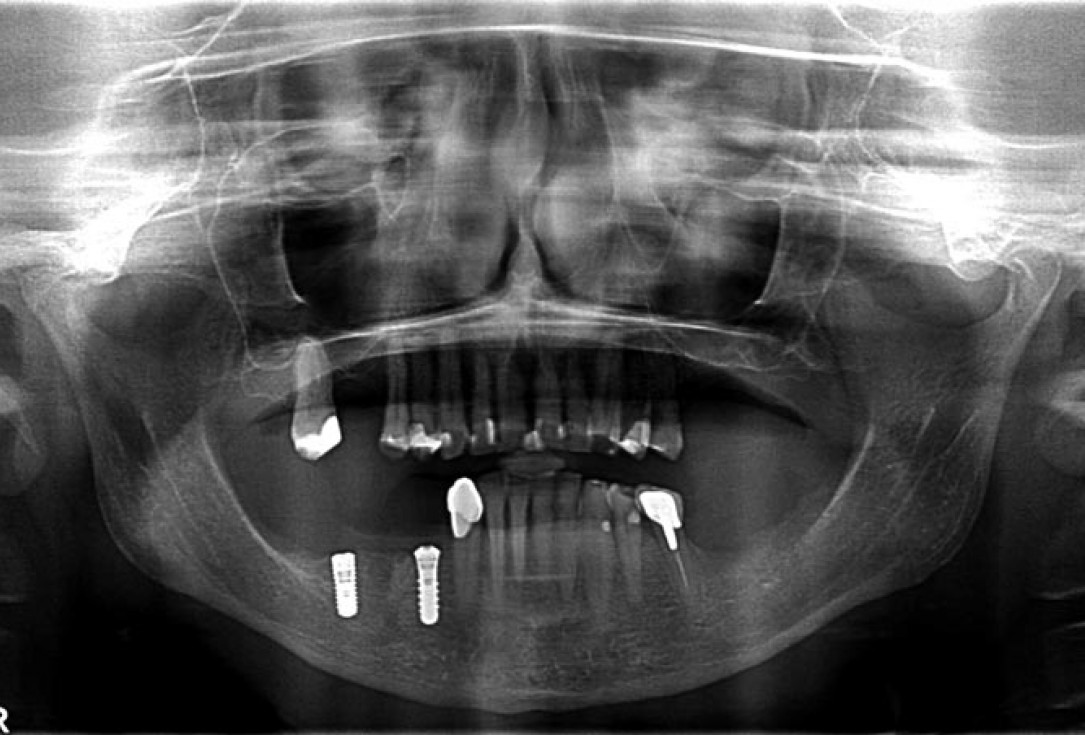

02/14 - Preoperative radiological situation

Block augmentation with maxgraft® in the mandible - PD Dr. Dr. F. Kloss